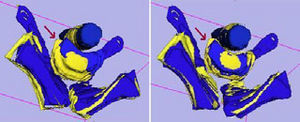

Boolean Combinations of Implicit Functions for Model Clipping in Computer-Assisted Surgical Planning

Publication: PLoS One. 2016 Jan 11;11(1):e0145987. PMID: 26751685 | PDF Authors: Zhan Q, Chen X. Institution: School of Mechanical Engineering, Shanghai Jiao Tong University, Shanghai, China. Background/Purpose: This paper proposes an interactive method of model clipping for computer-assisted surgical planning. The model is separated by a data filter that is defined by the implicit function of the clipping path. Being interactive to surgeons, the clipping path that is composed of the plane widgets can be manually repositioned along the desirable presurgical path, which means that surgeons can produce any accurate shape of the clipped model. The implicit function is acquired through a recursive algorithm based on the Boolean combinations (including Boolean union and Boolean intersection) of a series of plane widgets' implicit functions. The algorithm is evaluated as highly efficient because the best time performance of the algorithm is linear, which applies to most of the cases in the computer-assisted surgical planning. Based on the above stated algorithm, a user-friendly module named SmartModelClip is developed on the basis of Slicer platform and VTK. A number of arbitrary clipping paths have been tested. Experimental results of presurgical planning for three types of Le Fort fractures and for tumor removal demonstrate the high reliability and efficiency of our recursive algorithm and robustness of the module. Funding:

|

A snapshot of the module SmartModelClip in 3D Slicer. On the left is the operator command view that users can create and manipulate clipping path and thickness plane(i.e., they can create, hide and delete plane widgets). Users can also reverse the directions of the axes of the both clipping path and thickness plane widget. On the right is the scene that users can interact with the clipping path. They can specify the fiducial points that position the clipping path and modify the boundary of the clipping path by dragging the handles to obtain the desirable clipping path. |